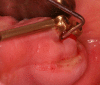

Peri-implant inflammations represent serious diseases after dental implant treatment, which affect both the surrounding hard and soft tissue. Due to prevalence rates up to 56%, peri-implantitis can lead to the loss of the implant without multilateral prevention and therapy concepts. Specific continuous check-ups with evaluation and elimination of risk factors (e.g. smoking, systemic diseases and periodontitis) are effective precautions. In addition to aspects of osseointegration, type and structure of the implant surface are of importance. For the treatment of peri-implant disease various conservative and surgical approaches are available. Mucositis and moderate forms of peri-implantitis can obviously be treated effectively using conservative methods. These include the utilization of different manual ablations, laser-supported systems as well as photodynamic therapy, which may be extended by local or systemic antibiotics. It is possible to regain osseointegration. In cases with advanced peri-implantitis surgical therapies are more effective than conservative approaches. Depending on the configuration of the defects, resective surgery can be carried out for elimination of peri-implant lesions, whereas regenerative therapies may be applicable for defect filling. The cumulative interceptive supportive therapy (CIST) protocol serves as guidance for the treatment of the peri-implantitis. The aim of this review is to provide an overview about current data and to give advices regarding diagnosis, prevention and treatment of peri-implant disease for practitioners.